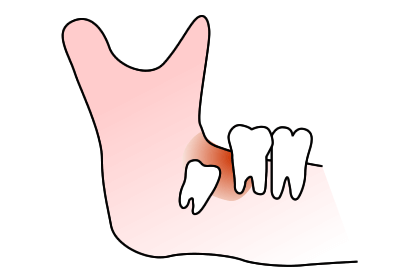

親知らずを抜かなくてはいけないのか、悩んでる方は多いと思います。親知らずを放っておくと次のようなトラブルを起こす可能性があります。

親知らずは歯ブラシが届きにくく虫歯になりやすい歯です。治療も困難で、むし歯になったら抜歯するのが一般的です。(生え方や咬み合わせにより、治療して保存する場合もあります)

上の写真のケースでは、親知らずが横を向いて前の歯との間に食渣が非常に挟まりやすい状態になっていました。患者さんご本人も気になっていましたが放置されていたため、左下の歯が痛くなり、来院された時には親知らずの前の歯が神経に達するほどのむし歯になっていました。

ここが虫歯になると、神経に近接しているため治療が困難になり、神経の治療を行っても予後が悪くなります。